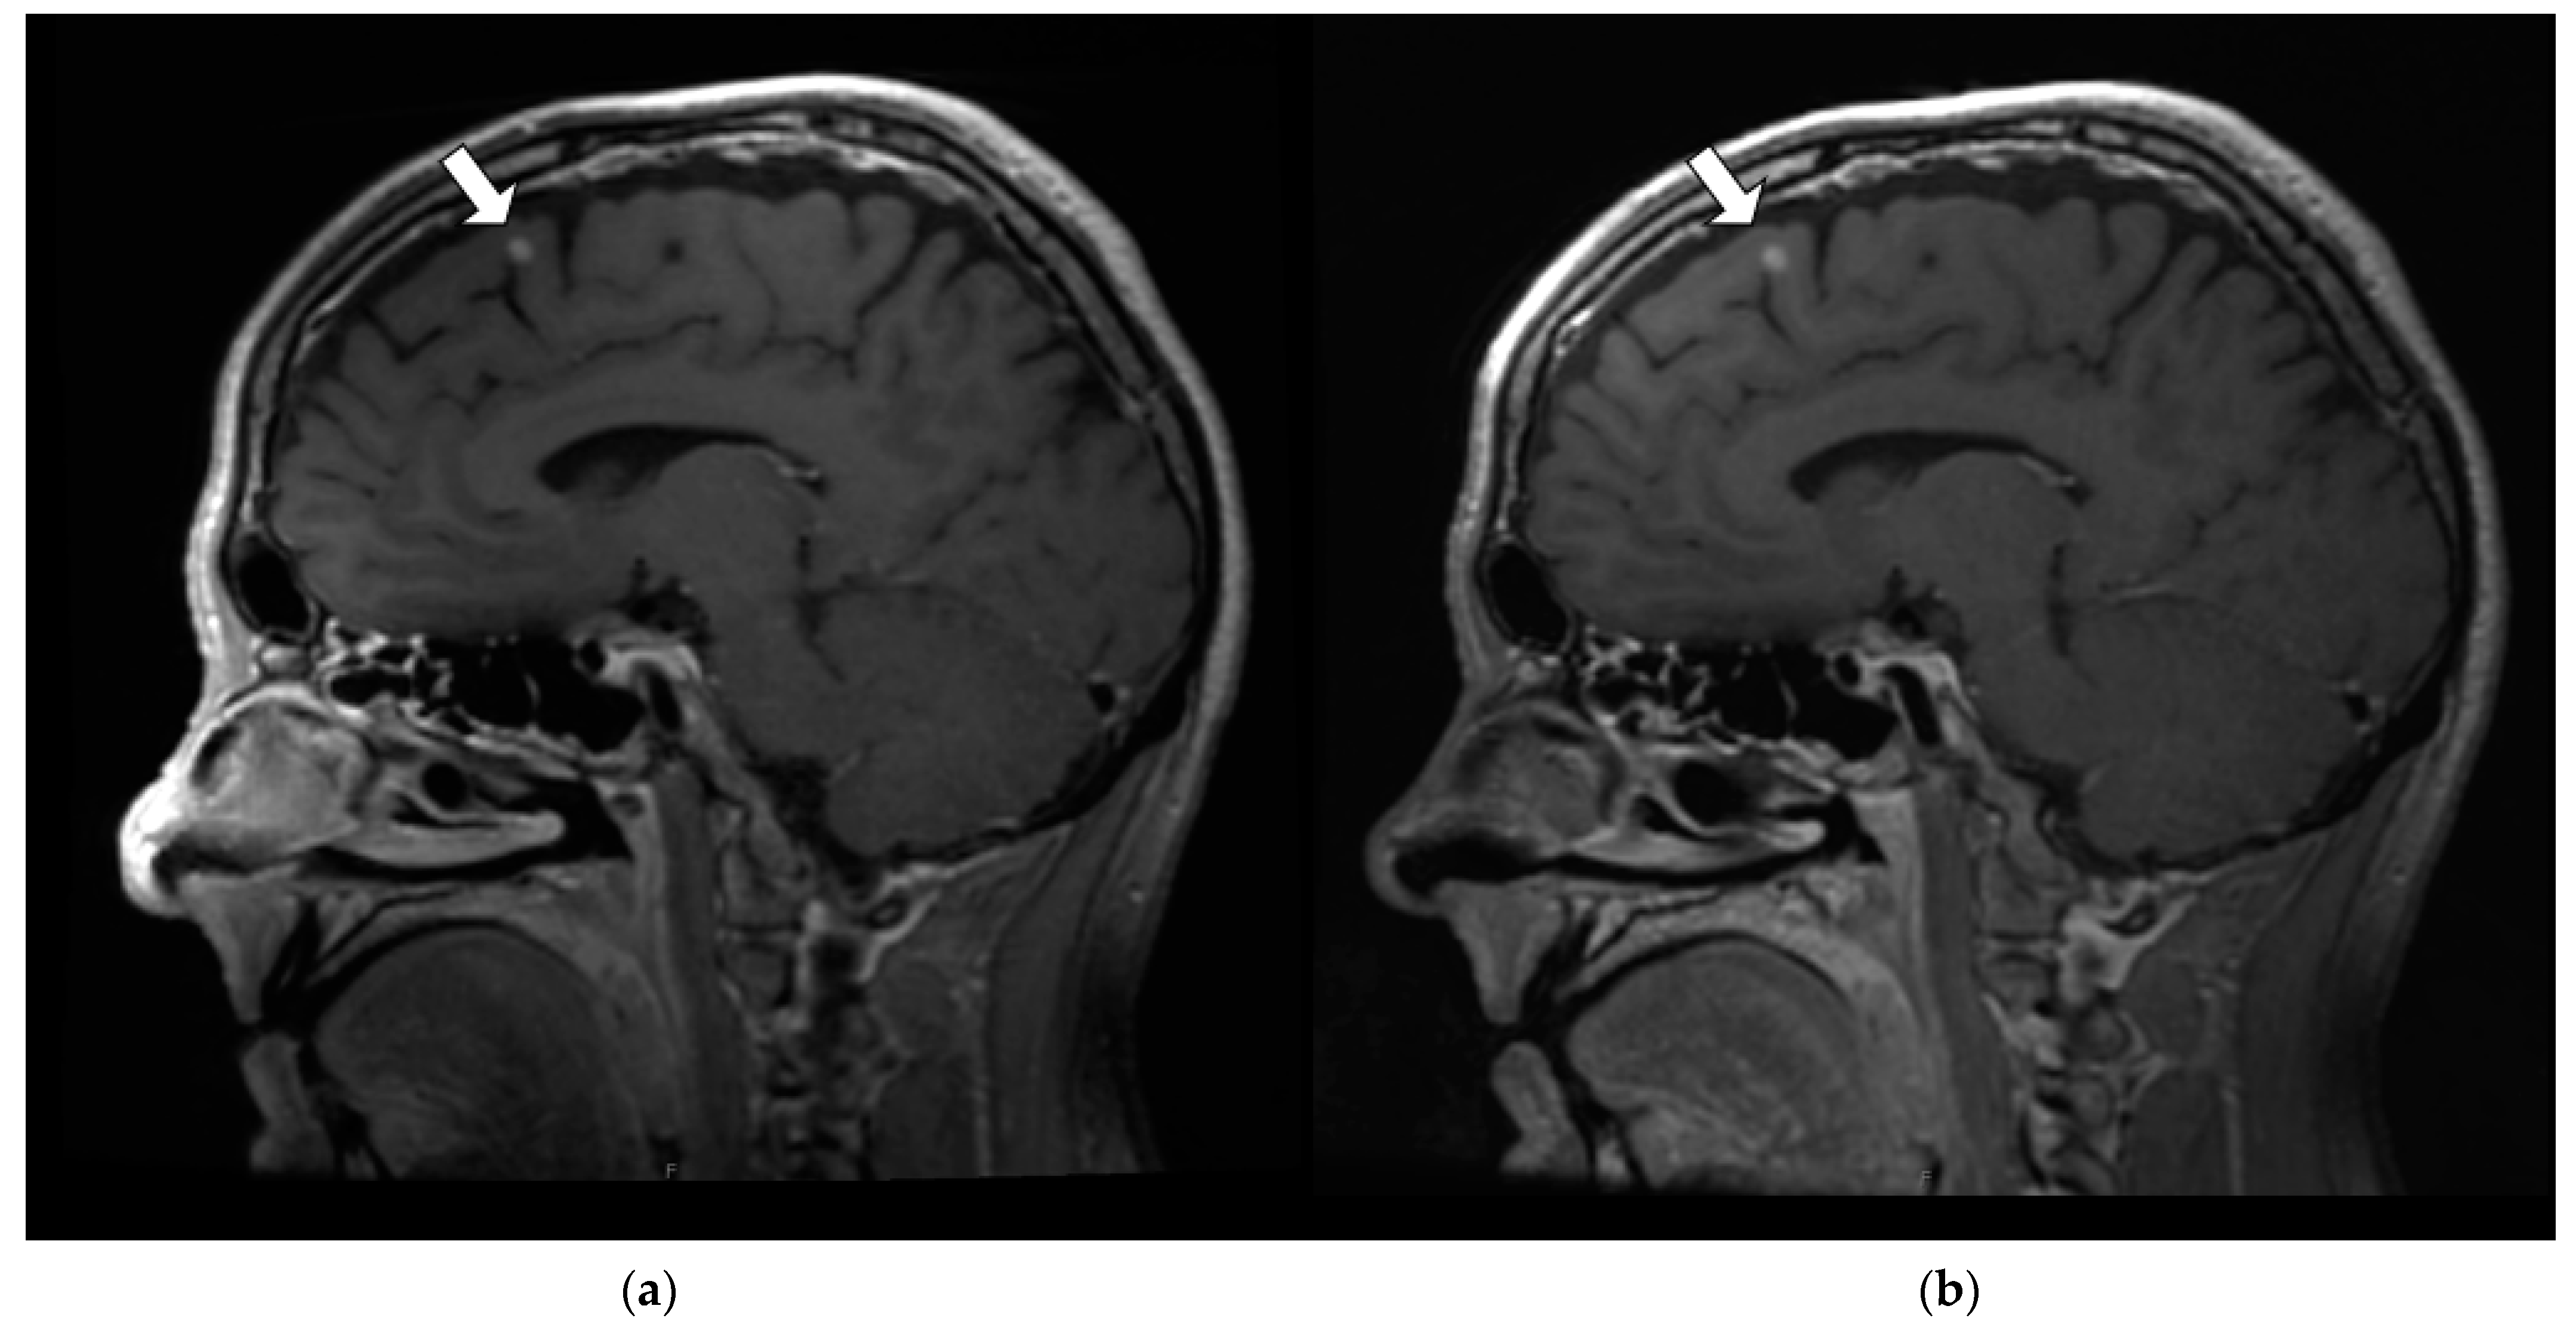

3.3.1. Margin Delineation

3.3.2. Artifact Enhancement